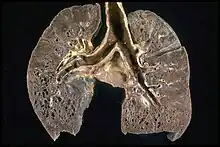

Respiratory tract

Localization to the lungs is by far the most common manifestation of sarcoidosis.[25] At least 90% of affected persons experience lung involvement.[26] Overall, about 50% develop permanent pulmonary abnormalities, and 5 to 15% have progressive fibrosis of the lung parenchyma. Sarcoidosis of the lung is primarily an interstitial lung disease in which the inflammatory process involves the alveoli, small bronchi, and small blood vessels.[27] In acute and subacute cases, physical examination usually reveals dry crackles.[26] At least 5% of persons suffer pulmonary arterial hypertension.[26][28] The upper respiratory tract (including the larynx, pharynx, and sinuses) may be affected, which occurs in between 5 and 10% of cases.[29]

The four stages of pulmonary involvement are based on radiological stage of the disease, which is helpful in prognosis:[30]

- Stage I: bilateral hilar lymphadenopathy (BHL) alone

- Stage II: BHL with pulmonary infiltrates

- Stage III: pulmonary infiltrates without BHL

- Stage IV: fibrosis